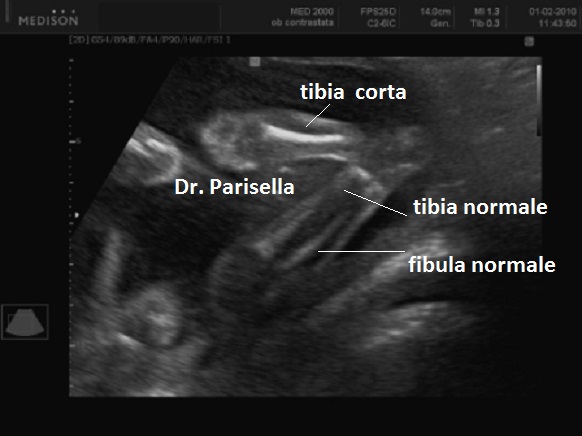

Sindrome di Werner - Sindrome ipoplasia della tibia-polidattilia - Nanismo Mesomelico di Werner   OMIM 188770

Segni principali:

ipoplasia tibia

polidattilia

pollice trifalangeo

Segni aggiuntivi:

sindattilia

ispessimento fibula